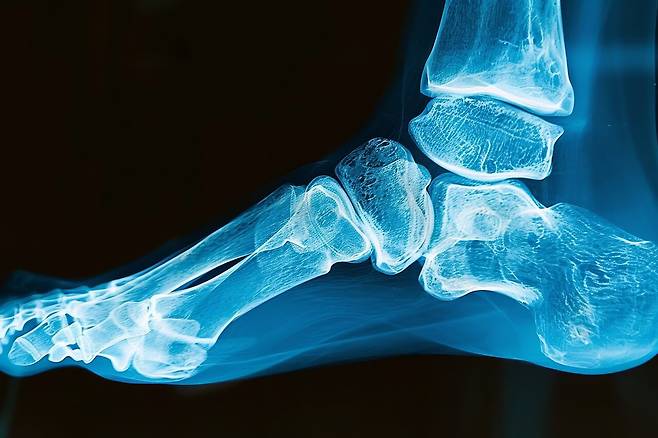

뼈와 뼈 사이를 연결하는 관절의 연골이 파괴되고 염증이 나타나는 질환을 '관절염(Arthritis)'이라 한다. 흔히 무릎이나 척추, 엉덩이를 생각하지만, 발목에서도 관절염이 발생한다.

발목관절염이란 정강이뼈와 발뼈를 잇는 발목관절에 염증이 생기는 질환이다. 주로 발목의 통증, 부기가 나타나고, 발목을 움직일 수 있는 운동범위가 제한된다. 유병률은 연구마다 차이가 있지만 전체 인구의 약 1%에서 3.4% 사이로 발생하는 것으로 알려져 있다.

다른 관절염은 퇴행성으로 발생하는 경우가 많다. 발목관절염 역시 퇴행성이나 류마티스 질환, 통풍 등으로 발생할 수 있다. 하지만 그보다는 발목 골절이나, 인대파열 등의 외상 후유증으로 발생하는 경우가 70% 이상이다.